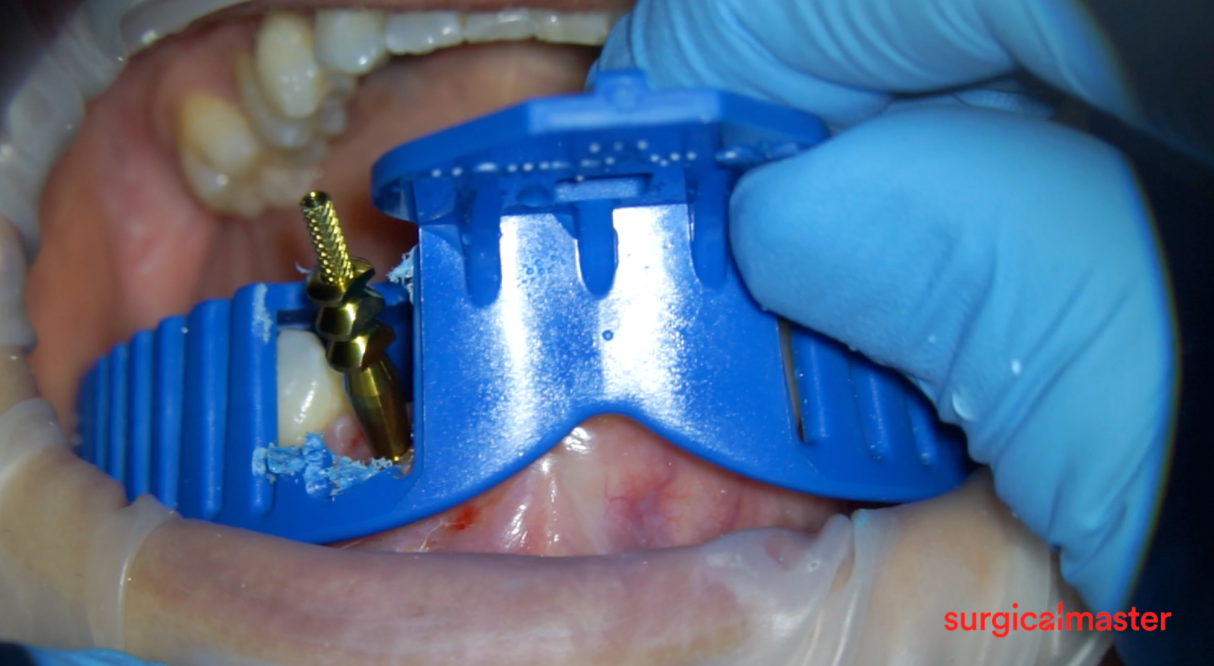

🎯 Restoring a severely facially-tilted implant in the esthetic zone (HD microscope footage).